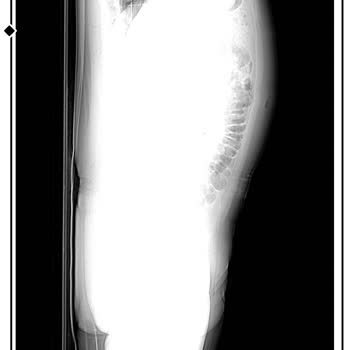

18 Ocak 2026 sabah saat 07.00 civarında Taksim’deki The Elysium Hotel’de 2203 numaralı standart odanın banyosunda çok ciddi bir kaza geçirdim. Banyodaki fayanslar son derece kaygandı, zeminde kaymayı önleyici hiçbir malzeme yoktu ve tutunabileceğim herhangi bir aparat da bulunmuyordu. Duş sırasında ...